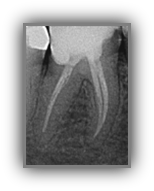

Wurzelkanalbehandlung / Endodontie

Große Defekte, die durch Karies, Stürze oder schwere Parodontitis verursacht werden, können den Zahnnerv schwer schädigen und somit die Erhaltungswürdigkeit des Zahns gefährden. Oft werden solche Zähne einfach entfernt und Patient*innen leiden unter Zahnverlust – wir wollen Zähne erhalten und nicht ersetzen. Die Wurzelkanalbehandlung ist eine zahnerhaltende Behandlungsalternative zum Ziehen des betroffenen Zahns. Im Bereich der konservierenden Zahnheilkunde ist die Wurzelkanalbehandlung eine vielversprechende Methode, einen geschädigten Zahn zu erhalten und so Zahnverlust möglichst zu vermeiden.